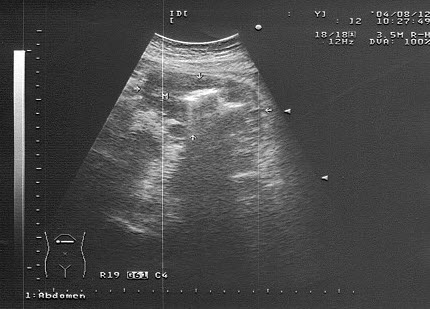

男性,右侧阴囊空虚,左侧可触及,于腹腔见一个椭圆形低回声光团,边界清晰,回声尚均匀,CDFI:血流信号丰富。如图所示,考虑为()

A.隐睾并精原细胞瘤

B.腹腔囊肿

C.腹腔淋巴结

D.畸胎瘤

E.腹腔淋巴瘤